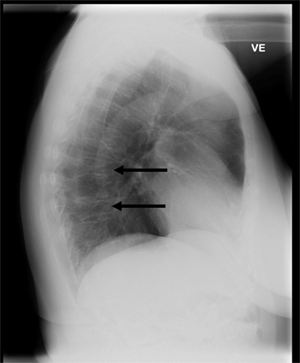

A 51-year-old Greenlandic woman attended the outpatient clinic at the local hospital in Sisimiut, Greenland, due to lower back pain. The back pain had persisted for months. No trauma could be recalled and the patient had not carried any heavy weight. On the physical examination the patient had normal gait, no neurological deficits and normal muscle strength. Laboratory results showed a low vitamin D level (P-25-OH-vitamin D 28 nM, reference >50 nM) but normal total S-calcium level (2.40 mM, reference 2.2-2.7 mM), S-calcium++ (1.26 mM, reference 1.17-1.34 mM), S-phosphate (1.2 mM, reference 0.8-1.5 mM), S-parathyroid hormone 1-84 (2.6 pM, reference 0.3-14.6 pM), S-thyrotropin (0.67 miu/L, reference 0.4-3.8 miu/L), erythrocyte sedimentation rate (7 mm, reference <30 mm), S-creatinine (73 µM, reference 44-114 µM) and hemoglobin (9.0 mM, reference 7.0-9.4 mM). A radiograph of the lumbar spine showed severe spondyloarthrosis and slight scoliosis but all vertebrae were of normal height and without fractures. A chest radiograph was taken (Fig1), which demonstrated compression fractures of the seventh and ninth thoracic vertebrae with a reduction of anterior height of the vertebral bodies of 50% and 40% respectively. The patient's risk factors for osteoporosis are listed in Table 1 along with a line-up of the risk factors included in the QFracture algorithm and in the FRAX fracture risk calculator. Dual energy X-ray absorptiometry for measurement of bone density is not available in Greenland.

Figure 1: Lateral chest radiograph taken at Sisimiut Hospital on the west coast of Greenland in a patient with back pain but no trauma. It illustrates two vertebral fractures that are diagnostic of osteoporosis in the patient. Risk factors for osteoporosis included smoking, parental hip fracture and female gender. Vitamin D level was in the range of insufficiency (28 nmol/L) but sedimentation rate was normal, and serum calcium, alkaline phosphatase and parathyroid hormone were within the reference ranges.